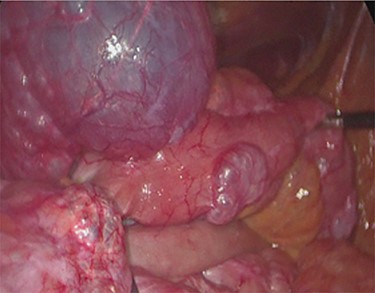

Unfortunately, once he returned home his temperature started to rise up to 38°C and he was readmitted to the hospital. A new contrast-enhanced Chest/Abdomen CT showed a bilateral pneumonia and a massive amount of intraperitoneal free gas, mainly in the abdominal upper quadrants (Fig. 2). No fat stranding, nondilated bowel, no vascular abnormalities and no free fluid were detected. Although the CT showed an evident worsening, the patient still remained completely asymptomatic on physical examination. Accordingly, he started to be treated with meropenem for pneumonia (Escherichia coli was isolated into the sputum) and he finally agreed to underwent diagnostic laparoscopy. Surprisingly, that was definitely not a case of pneumoperitoneum but an idiopathic PCI as we found multiple intramural air content cyst, about 2–3 cm in diameter, all around the small bowel loops and mesentery (Fig. 3). No intra-abdominal maneuvers were made. The patient had an unremarkable recovery (Clavien–Dindo classification grade was 1) [3] and he was discharged home on postoperative Day 15 in well condition, once he had recovered from pneumonia.

Intra-operatory findings of pneumatosis cystoides intestinalis of the small bowel.

PCI was ultimately identified retrospectively using lung window settings.

PCI first documented by Du Vernoy in 1783 [4] refers to the intraoperative or radiological findings of intramural gas-filled cysts in the bowel wall (Fig. 4). PCI can easily mimic pneumoperitoneum on radiological imaging as CT, being a very sensitive examination, may show even minimal circumferential gas collections outside the bowel lumen or misrepresent some findings [5]. Liu et al. [6] found that PCI was misdiagnosed as a surgical abdomen in up to 27% of cases resulting in unnecessary operation. It is important to differentiate idiopathic PCI with a secondary form of this condition known as pneumatosis intestinalis which is not in fact a disease but a rare finding characterized by the presence of gas in the submucosal and/or subserosal of the bowel wall that may result from an underlying pathological process (Table 2). PCI has a reported incidence in general population of 0.03% on autopsy series and up to 0.37% in CT series. Its prevalence is still unknown [7]. However, Adachi et al. [8] in a retrospective, single-center study found 24.7% of PCI cases in the selected group affected by pneumoperitoneum. PCI involves most commonly the small and large bowel (respectively 42% and 36% of cases; in 22% is concomitantly present), but could also involve the mesentery and omentum [7]. Physiopathology remains still unclear although some hypotheses have been proposed such as: the ‘mechanical theory’ where an increased pressure of intraluminal gas secondary to mechanical problems breach the mucosal or serosal layers (i.e. blunt trauma, persistent vomiting, ileus or endoscopy); the ‘bacterial theory’ where an excess of intraluminal bacterial production of nitrogen gas diffuse through the bowel wall; the ‘chemical theory’ where malnutrition can prevent the digestion of carbohydrates and increased bacterial fermentation in the intestine; the ‘pulmonary theory’ that refers to increased intraluminal bowel pressure due to the respiratory system [9].